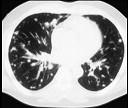

问题 女,72岁,咳嗽,胸闷,呼吸困难1月余,1年前行结肠癌根治术,CT检查如图,请选择最可能的诊断 ( )

选项 A.肺癌 B.肺转移瘤 C.尘肺 D.间质性肺炎 E.粟粒型肺结核

答案 B